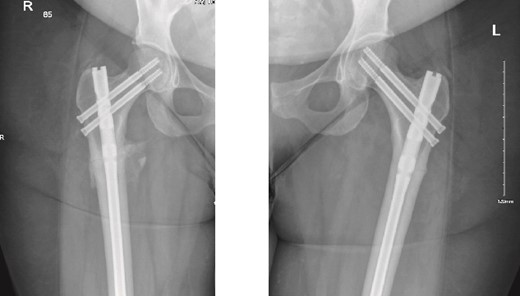

The left side was then prepped and draped. The same procedure was performed, with the nail size changed to 9 mm x 360 mm. Two proximal recon screws (90 mm) were inserted, followed by two distal screws. After fixation, the wound was irrigated, and closure was completed using Vicryl sutures for the subcutaneous tissue. The skin was closed with clips, and a sterile dressing was applied. The patient was extubated and transferred to her bed in stable condition, then moved to the post anesthesia care unit in stable condition. Immediate post-operative X-rays of both the right and left femurs are shown in Fig. 2.

Anteroposterior (AP) view of the right and left femurs after CRIF with IM nail.